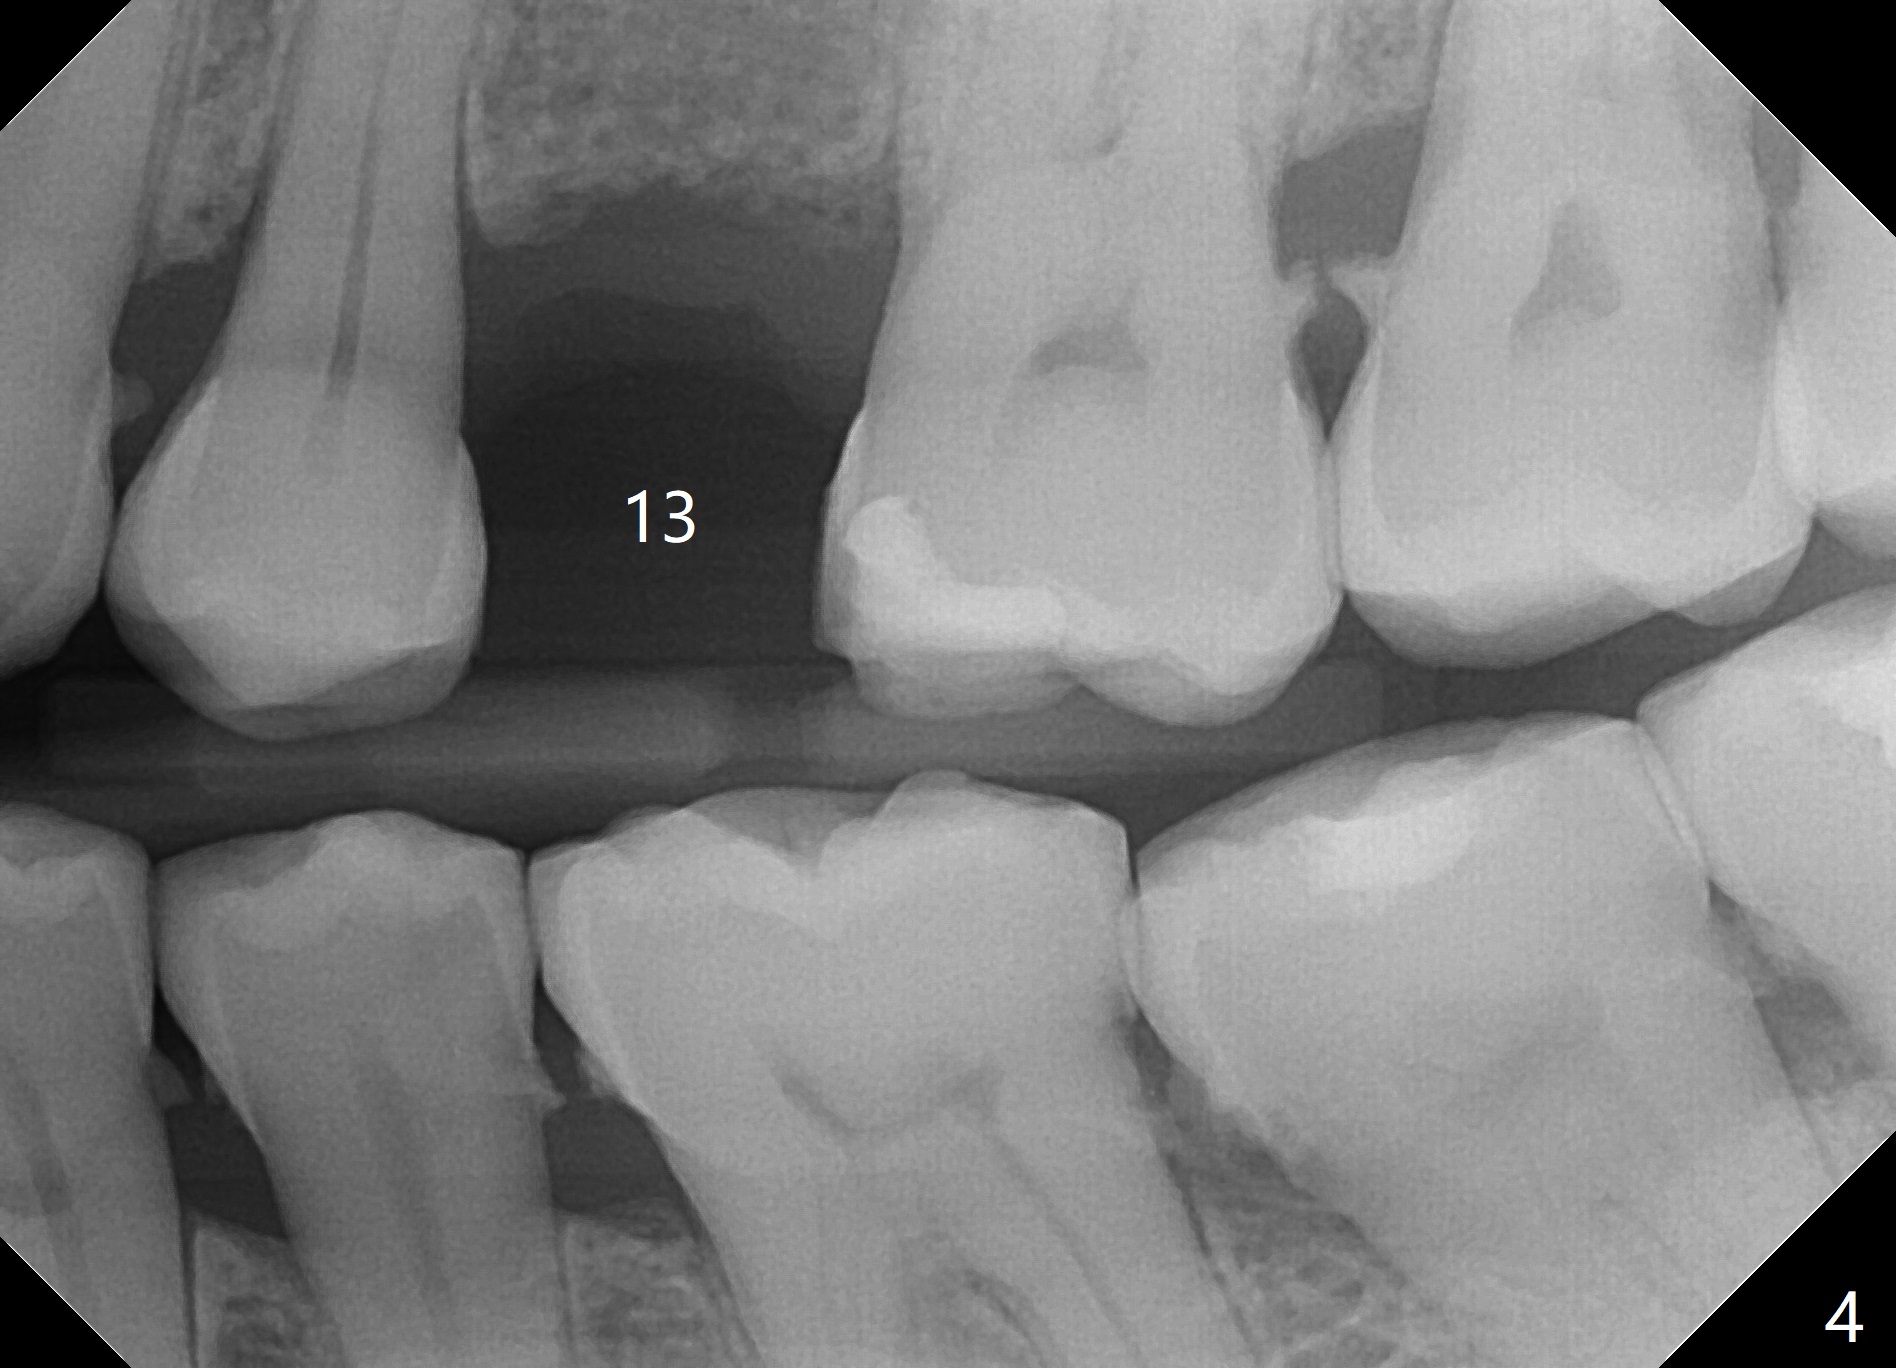

Concern of a 48-year-old woman is the exfoliating central incisor (Fig.1). After SRP (Fig.3,4), a long implant will be placed for stability (Fig.2), considering a posterior missing tooth (Fig.4).